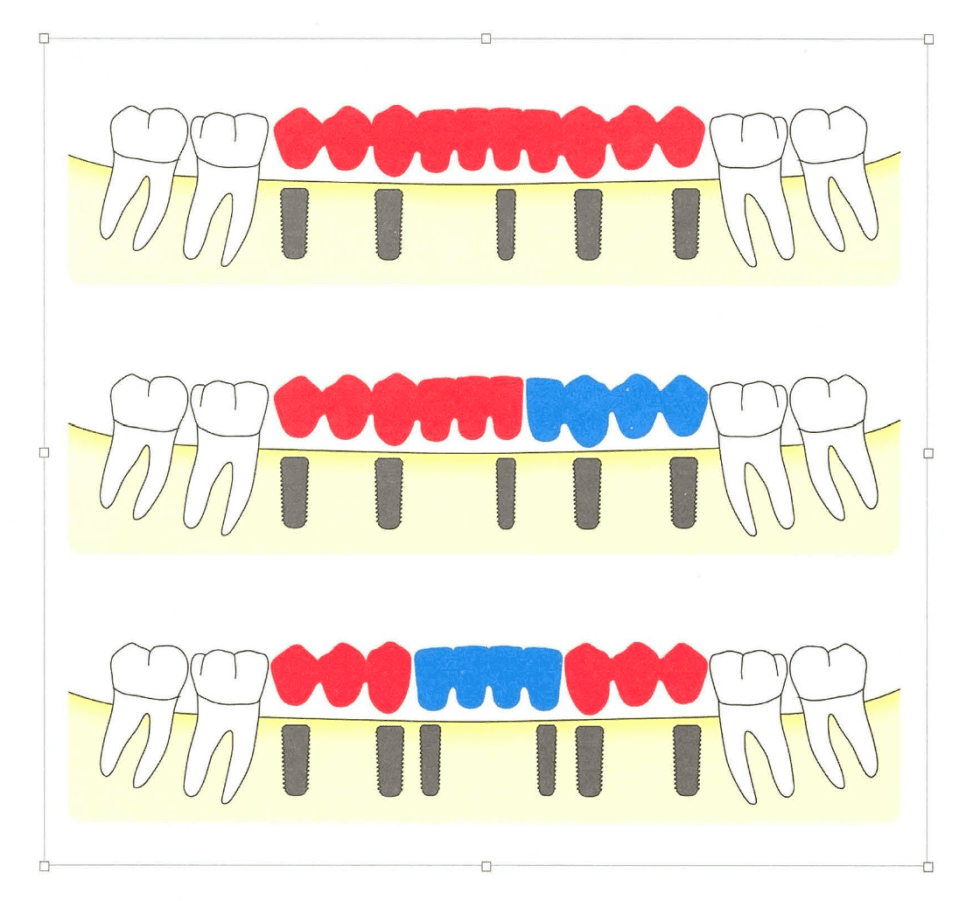

[그림 1] 두 개의 임플란트를 대구치 부위에 배치하려면 최소 13~14mm의 근원심 공간이 필요합니다.

공간 ≥ 13~14mm

임플란트 2개를 각각 단관으로 수복. 교합력이 분산되고 유지관리가 쉬워집니다.

공간 < 13mm

임플란트 1개에 교합면을 넓힌 단관 수복, 혹은 소구치 3개 형태로 재배열해 수복하는 쪽이 유리합니다. 무리한 2개 배치는 임플란트 사이 거리 부족으로 변연골 흡수를 가속화할 수 있습니다.

구치부 3개 상실 — 반드시 3개를 심을 필요는 없습니다

구치부 3개 상실이라고 해서 반드시 임플란트 3개를 모두 심어야 하는 것은 아닙니다. 양쪽 끝에 2개를 심고 중간을 pontic으로 연결하는 3-unit 설계가 임상에서 널리 쓰이며, 세 가지 실질적 이점이 있습니다.

- 수술 횟수·비용·회복 기간 감소 — 식립 개수가 줄면서 전신 부담이 작아집니다.

- 보철물 적합도 향상 — 임플란트가 너무 많이 나란히 배치되면 인상 정밀도와 패시브 핏 확보가 어려워집니다.

- 잇몸 건강에 유리 — 임플란트 사이 치간 유두(papilla)보다 임플란트–pontic 경계의 연조직 형태가 상대적으로 더 안정적입니다.

⚠️ 단, 상악 구치부처럼 골질이 약하거나 상악동 골이식이 필요한 증례에서는 교합력 분산을 위해 3개를 모두 심는 편이 안전합니다. “항상 2개 + pontic” 같은 규칙이 아니라 환자별 골질·교합력 평가가 우선입니다.